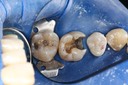

Scott Kanamori #12 caries removal